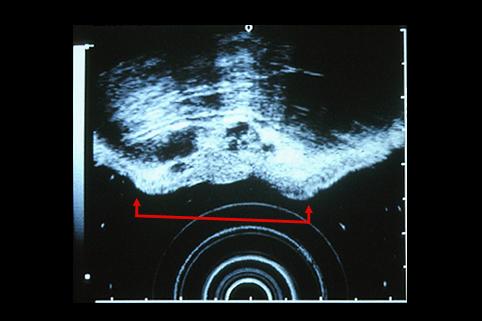

疾患(病理主体)の分類悪性上皮性腫瘍/腺癌

部位(臓器別)胃(部位)/胃角

検査方法エコー

腫瘍の肉眼分類0型(表在型)/IIa型(IIa+IIc)

病変の最大径(ミリ)30〜34

腫瘍の深達度m